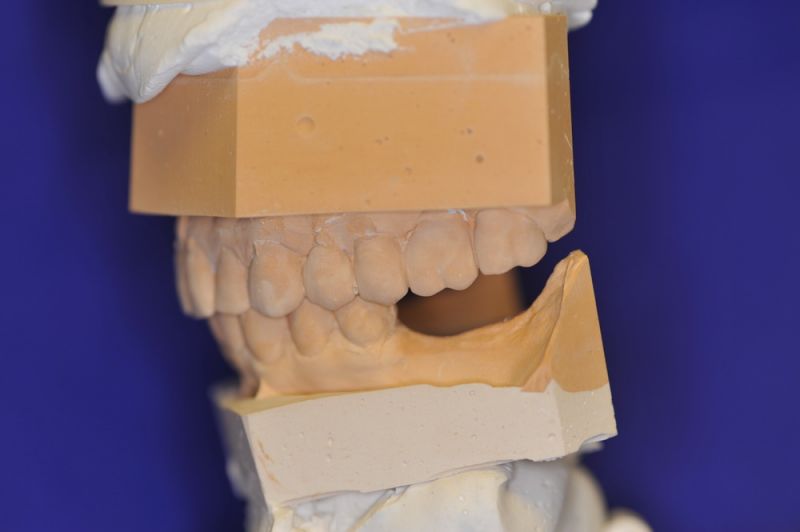

Die Problematik der Implantatversorgungen kann man in einer Analogie folgendermaßen darstellen. Die räumlich beengten Zustände gleichen dem Tanz eines Paares auf einer Briefmarke, und der gleichzeitigen Schritt- und Fusshaltung, dass beim Tanzen die Schuhe geputzt werden können!